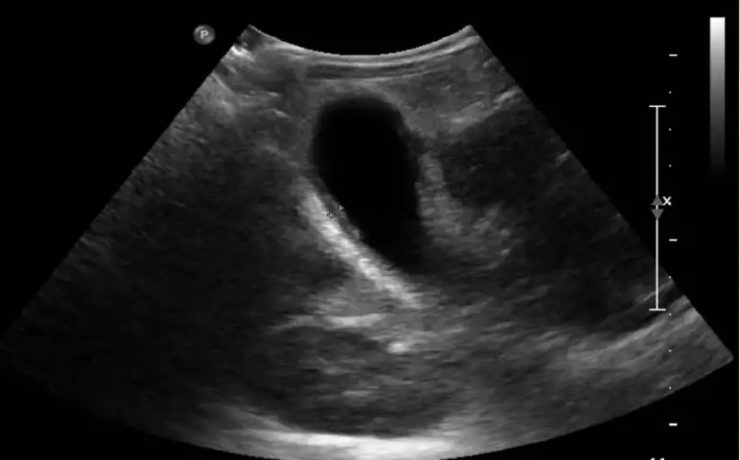

EL MODO A (modo de amplitud) fue el primer método utilizado para formar imágenes de ultrasonido. EL MODO B: modo de brillantez MODO M: modo de movimiento. Tiene su utilidad principal en ecocardiografía tanto en la fetal como en la del adulto. MODO B.- imagen en tiempo real. Al mover